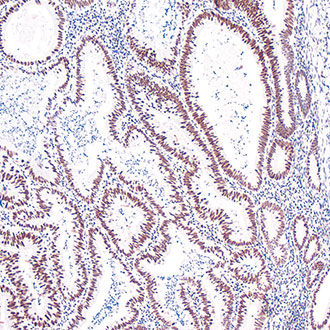

CDX-2

CDX-2 -